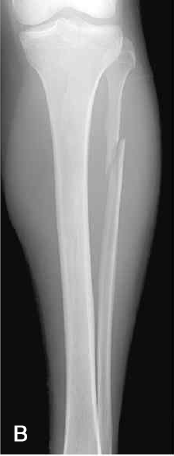

B는 Maisonneuve 골절로, 골간막의 파열과 비골 상단 1/3 부위의 골절을 나타낸다.

C는 Maisonneuve 골절로, 내측 복사뼈 골절 동반된 사진이다.